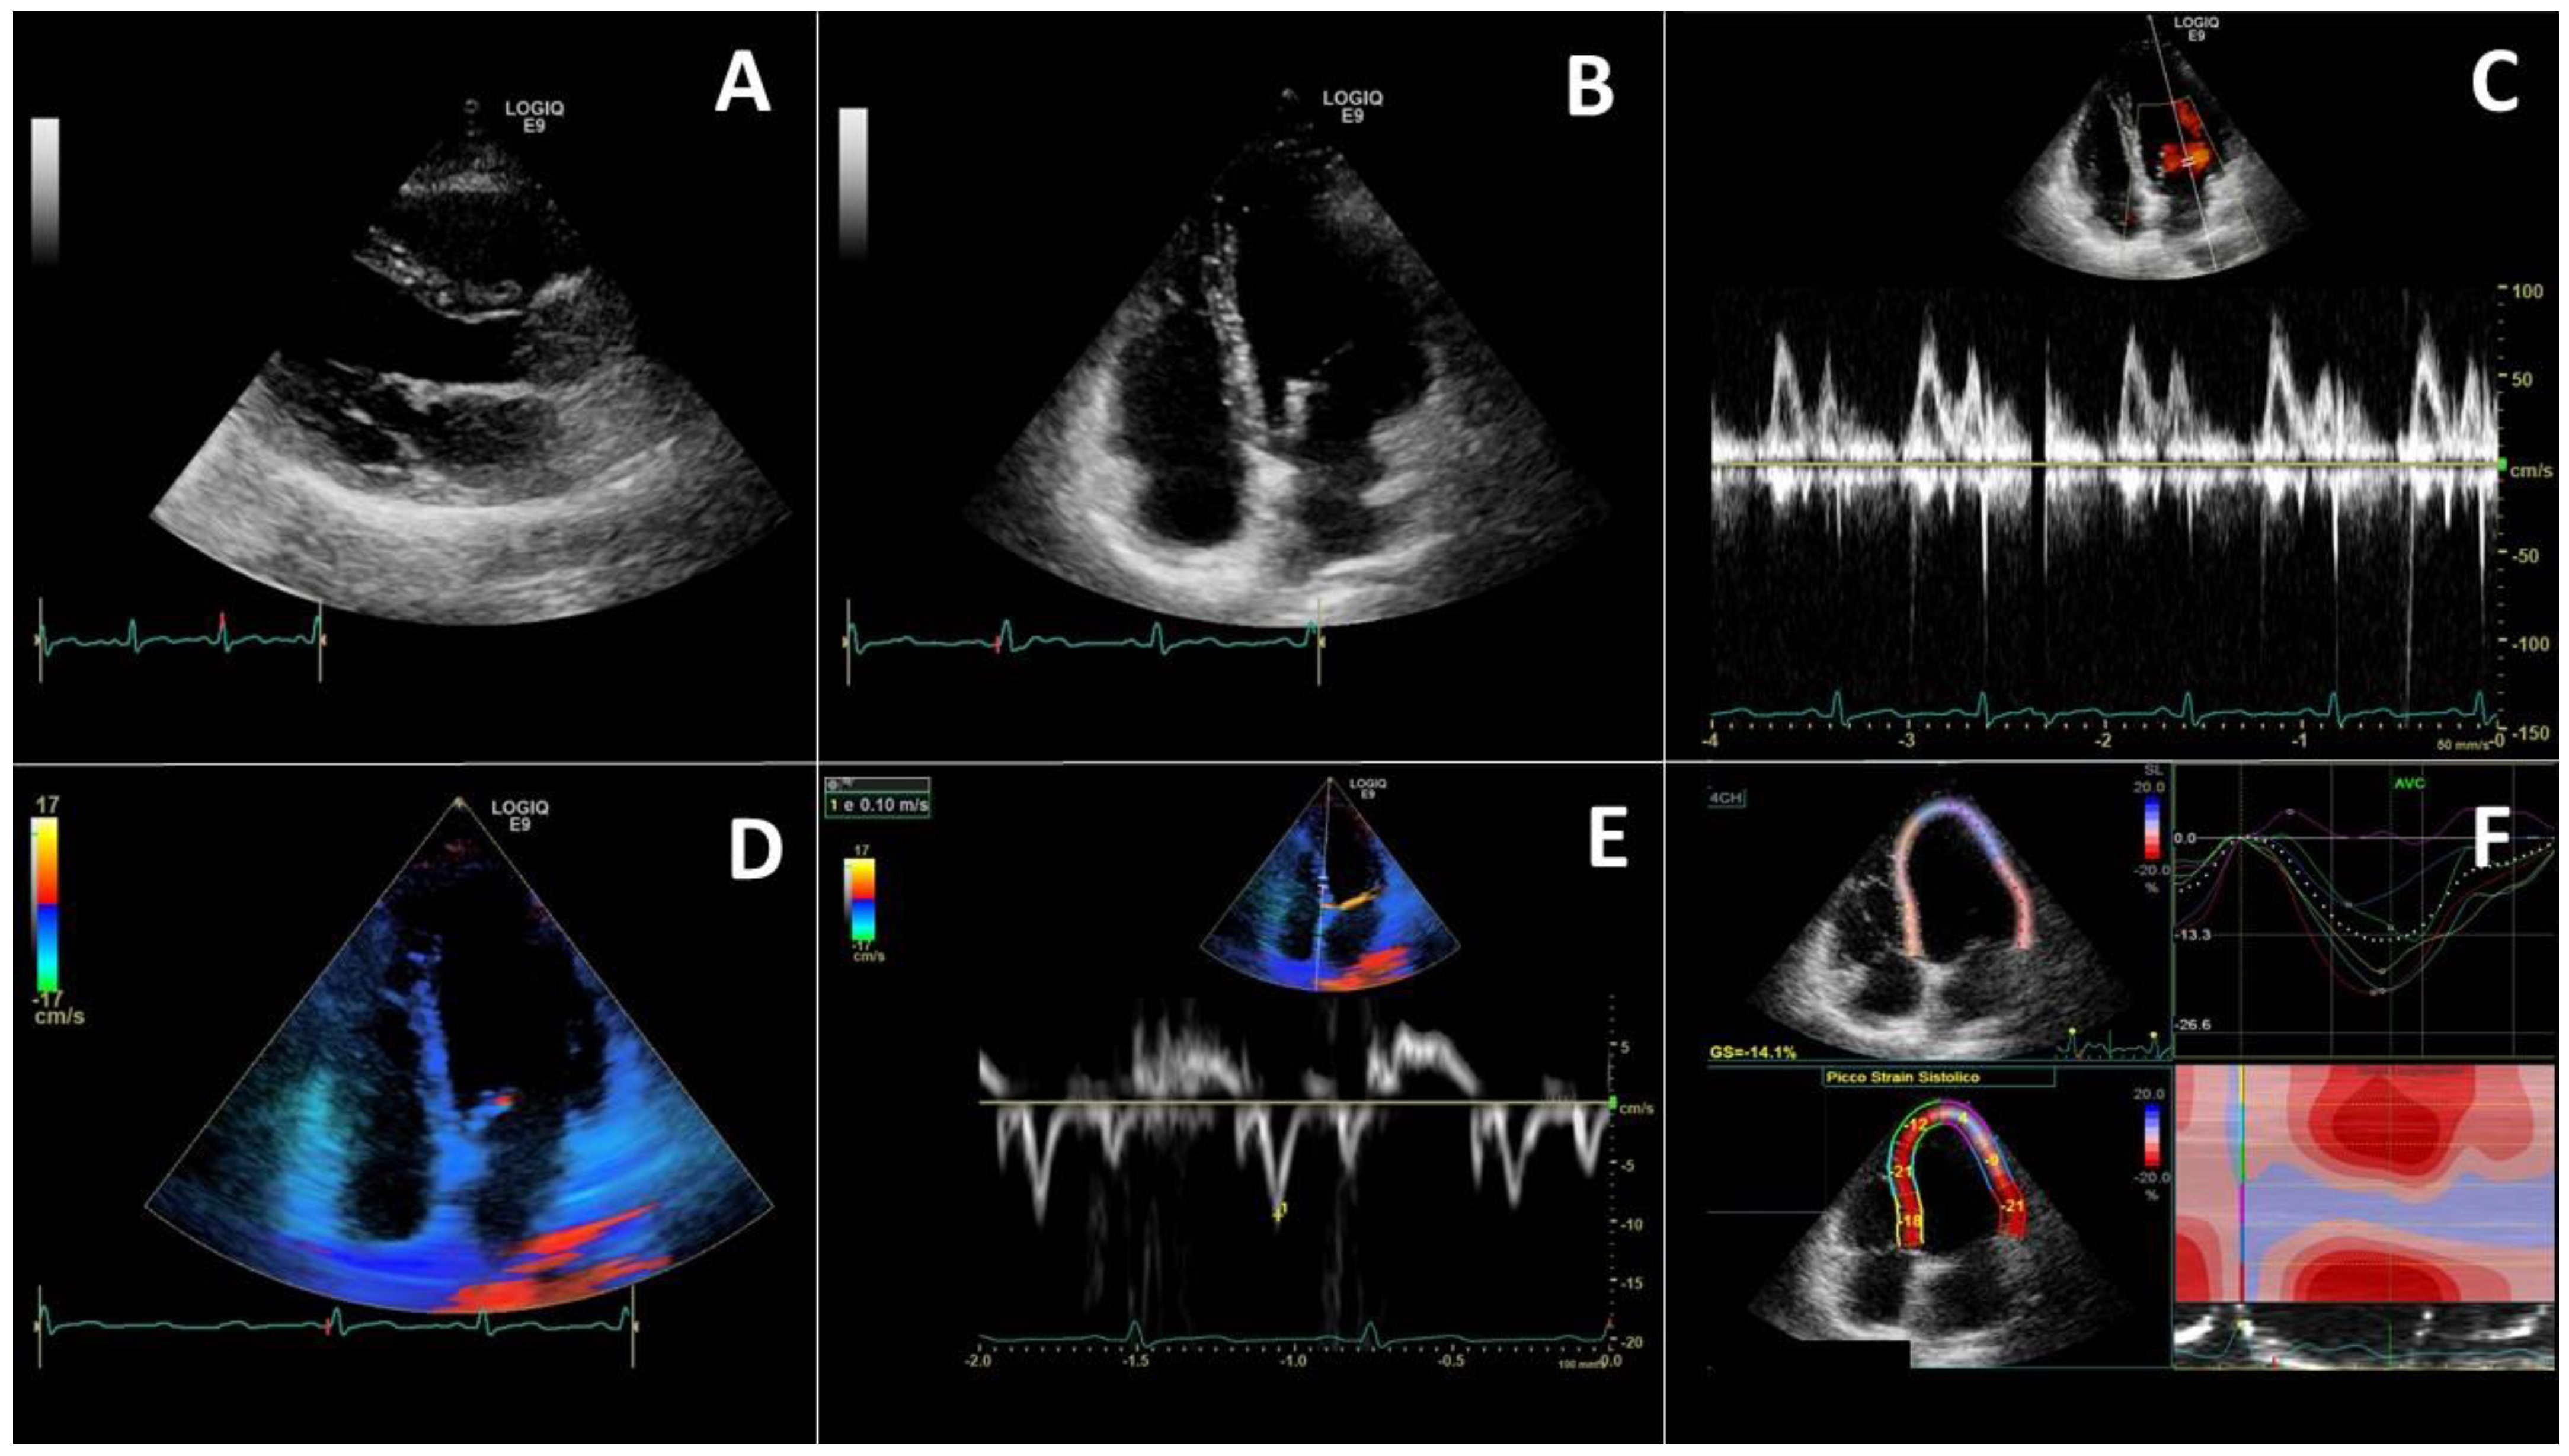

4.1. Left Heart Evaluation

8.1. Echocardiography Longitudinal Strain